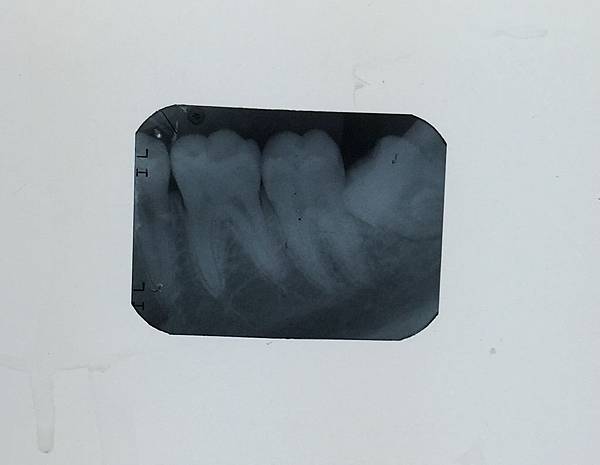

手術前確認X光片預先了解牙齒的位置與角度

側拍了解手術過程